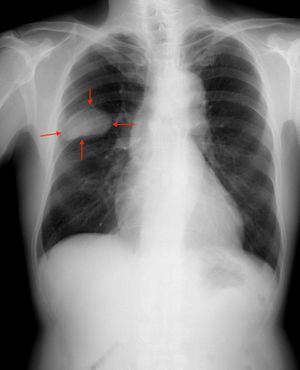

سرطان الخلايا الصغيرة Small-cell carcinoma (المعروف أيضا باسم "سرطان الخلايا الصغيرة الرئوي" small-cell lung cancer، أو "سرطان خلايا الشوفان " oat-cell carcinoma)، هو أحد أنواع السرطانات الخبيثة بشكل عالي والتي غالباً ما تنشأ داخل الرئة، [1] على الرغم من أنه يمكنه أن ينشأ في بعض الأحيان في مواقع أخرى من الجسم، مثل عنق الرحم[2] والپروستاتا[3] والجهاز الهضمي. بالمقارنة مع السرطانات غير صغيرة الخلايا، فإن سرطان الخلايا الصغيرة لديه وقت مضاعفة أقصر وارتفاع نسبة النمو، وانبثاث مبكر.

عادة ما يظهر سرطان الخلايا الصغيرة في الرئة في الشُعب الهوائية المركزية ويغزو الطبقة ما تحت المخاطية مما يؤدي إلى تضييق الممرات الهوائية. تشمل الأعراض الشائعة: السعال وضيق التنفس وفقدان الوزن والوهن. أكثر من 70٪ من المرضى الذين يعانون من سرطان الخلايا الصغيرة يتعرضون لمرض انبثاثي. يحدث الانبثاث في مواقع شائعة مثل: الكبد والغدة الكظرية والعظام والدماغ.

ينتشر سرطان الخلايا الصغيرة في أغلب الأحيان بسرعة أكبر وعلى نطاق أوسع من سرطان الرئة ذو الخلايا غير الصغيرة [8](وبالتالي تم تنظيمه بشكل مختلف). هناك عادة إصابة مبكرة في العقد اللمفاوية القمية و المنصفية.[7]